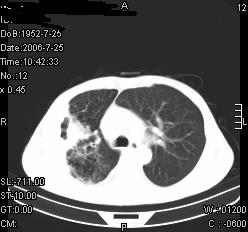

患者,男,54岁,咳嗦,咳痰20天。抗炎治疗2周。现esr76mm/h,目前患者症状明显好转,但发现两次ct片未见明显变化。两次分别做与7.25、7.31。第一次诊断右肺上叶炎症累计胸膜。大家看,从影像上内排除结核吗?

结核的可能性非常大,右上肺病变应该考虑干酪性肺炎。理由:

1.纵隔内多发淋巴结肿大。

2.esr76mm/h。

3.虽经抗炎治疗肺窗病灶有所吸收、减小,但纵隔窗病灶形态、密度、范围无明显变化。如果是单纯的大叶性肺炎,“抗炎治疗2周,目前患者症状明显好转”病灶应该基本消散了,至少也处于吸收消散期,密度变淡、范围变小。同时本病例所示其内的密度不均匀,见多发大小不一空洞样影也不符合大叶性肺炎吸收消散期表现。

病灶特点:片状 索条 结节混杂影,部分融合,密度不均,广泛累及相应胸膜.

临床治疗;二周未吸收.但症状好转.

多考虑:肺结核.